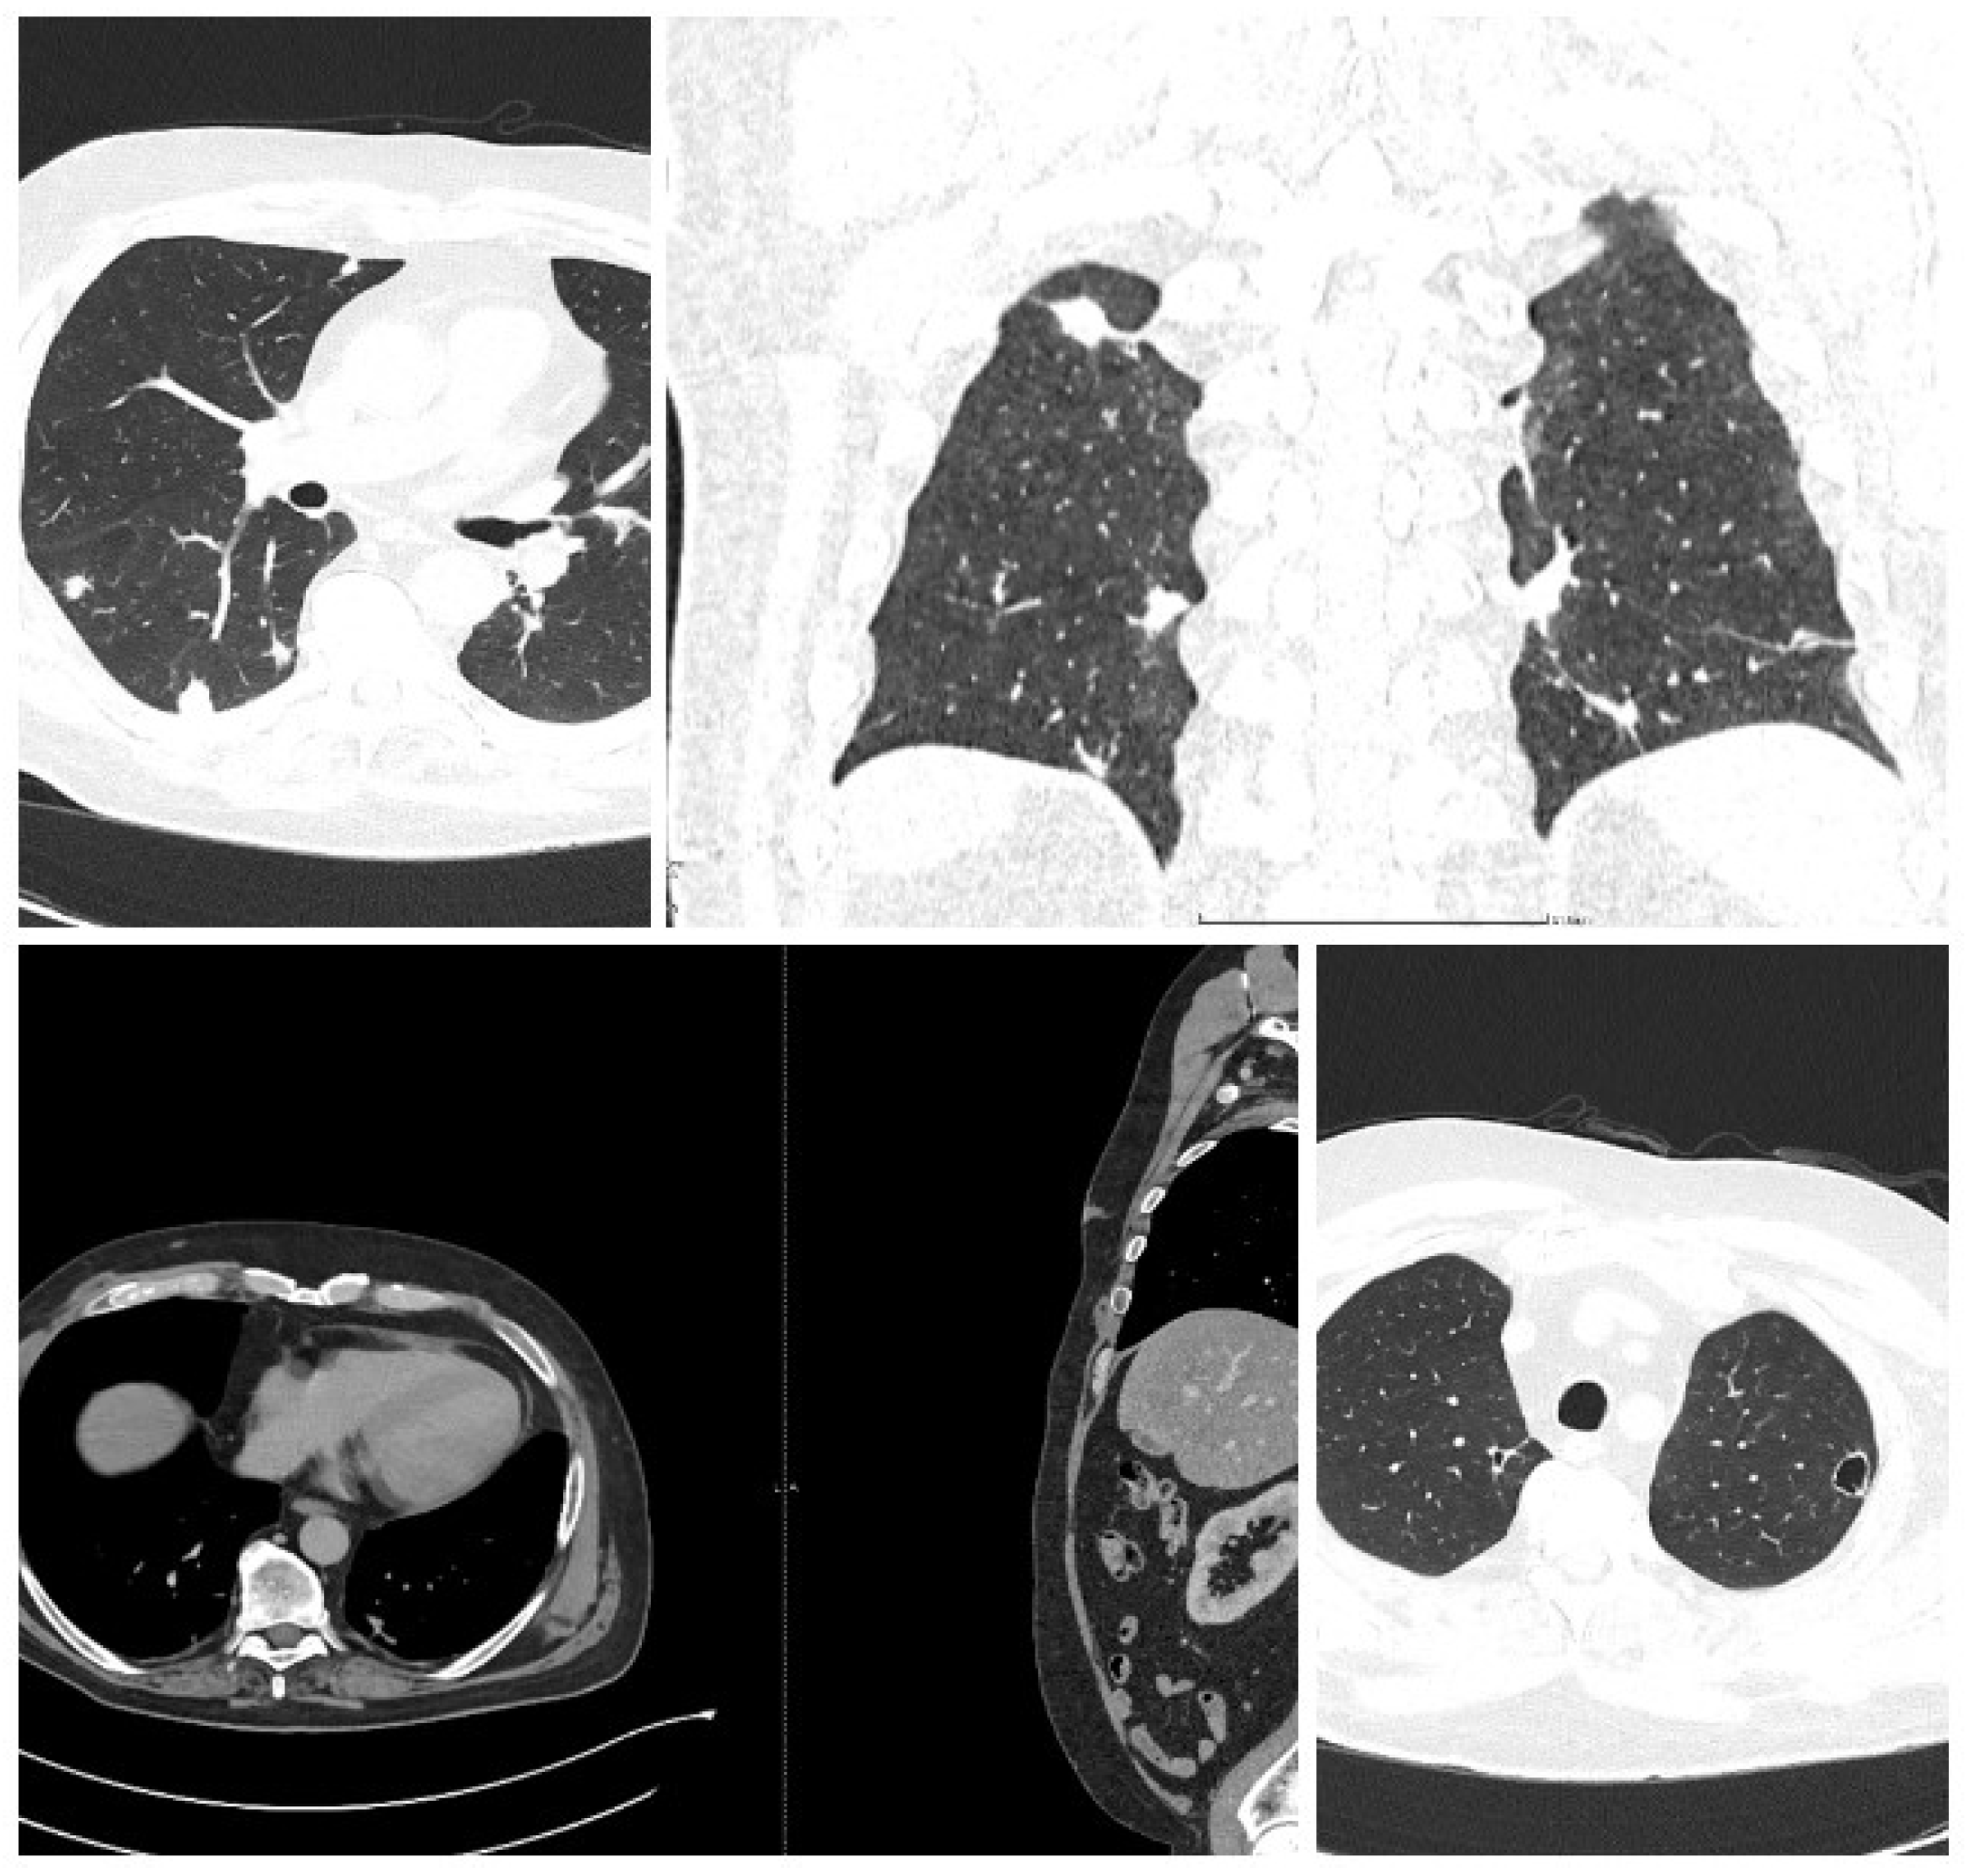

It was suspected that there was a metastatic tumor and a full-body CT scan was performed (Figure 2). The CT scan discovered multiple abscesses in the lungs and under the skin. A second contrast MRI (Figure 3) scan was conducted which revealed abscesses in all parts of the brain, including the right thalamus and left cerebellar hemisphere, with ring-like contrast-enhancing lesions. However, the lesions were relatively stable compared to the previous MRI.

The full-body CT scan showed multiple nodular cavitating lesions spread throughout the pulmonary area and several subcutaneous abscesses in various locations, with one notable abscess in the distal portion of the anterior serratus muscle and right pre-pectoral subcutaneous fat. Additionally, there were multiple nodules on the peritoneum and perisplenic fat, all measuring between 2-3 cm in diameter.

Figure 2. -CT (with contrast, showing disseminated lesions in lungs, abdomen, and soft tissues (the arrows indicate the evacuated abscess).

Figure 5. -Follow-up Ct at three months. The chest CT does not show any cavitating lesions, with residual scaring and healing processes of the lesions.